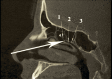

Endonasal endoscopic sinus surgery is the standard procedure for surgery of most paranasal sinus diseases. Appropriate frame conditions provided, the respective procedures are safe and successful. These prerequisites encompass appropriate technical equipment, anatomical oriented surgical technique, proper patient selection, and individually adapted extent of surgery. The range of endonasal sinus operations has dramatically increased during the last 20 years and reaches from partial uncinectomy to pansinus surgery with extended surgery of the frontal (Draf type III), maxillary (grade 3-4, medial maxillectomy, prelacrimal approach) and sphenoid sinus. In addition there are operations outside and beyond the paranasal sinuses. The development of surgical technique is still constantly evolving. This article gives a comprehensive review on the most recent state of the art in endoscopic sinus surgery according to the literature with the following aspects: principles and fundamentals, surgical techniques, indications, outcome, postoperative care, nasal packing and stents, technical equipment.